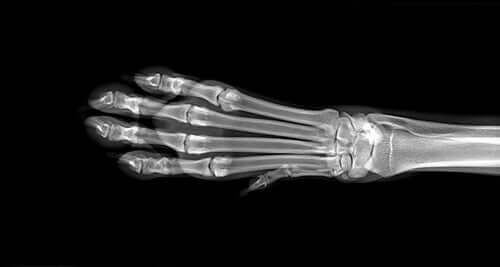

Først foretager din dyrlæge en række diagnostiske tests for at identificere årsagen til hævelsen. Disse vil omfatte blod- og urinprøver og mulige røntgenbilleder af lemmerne. Hvis disse tests ikke afslører noget afgørende, kan det være en god idé at tage en MR-scanning. Hvis de har mistanke om, at det er osteosarkom, udfører de en knoglebiopsi.